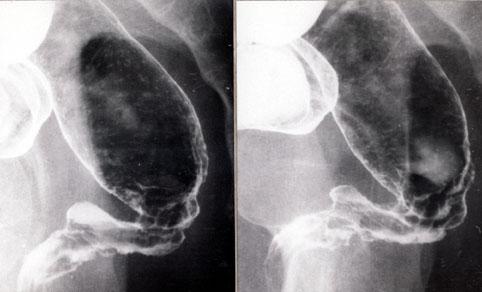

Rectal Crohns disease.

Inflammatory or ulcerative disease / lesions/Crohn disease

Large intestine(Colon)/Rectum

X-ray